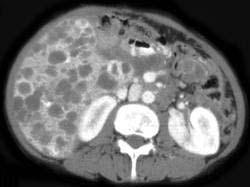

男,36岁,上腹部胀痛,CT检查如图所示,最可能的诊断是 ( )A、肝脓肿B、肝囊虫病C、肝癌D、多囊肝E、肝转移癌

问题 男,36岁,上腹部胀痛,CT检查如图所示,最可能的诊断是 ( )

选项 A、肝脓肿 B、肝囊虫病 C、肝癌 D、多囊肝 E、肝转移癌

答案 D